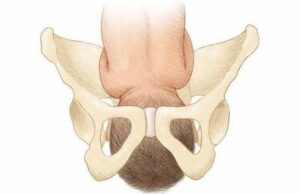

Боль при ходьбе и сидении у беременных – возможно это симфизит!

Незначительная боль в области таза во время родов — это нормально, если она не влияет на ваше общее самочувствие или способность двигаться. Однако иногда за ними скрываются симптомы лобкового симфиза — размягчение и расслоение костей лобкового симфиза. Он может развиваться постепенно или быстро, влияя на течение беременности и выбор способа родоразрешения. Особенности таза у беременных …